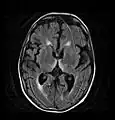

Axial MRI FLAIR image showing hyperintense signal in the mesial dorsal thalami, a common finding in Wernicke encephalopathy. This patient was nearly in coma when IV thiamine was started, he responded moderately well but was left with some Korsakoff type deficits.

Axial MRI B=1000 DWI image showing hyperintense signal indicative of restricted diffusion in the mesial dorsal thalami